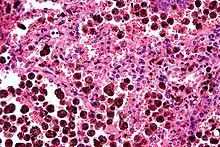

An alveolar macrophage (or dust cell) is a type of macrophage, a professional phagocyte, found in the pulmonary alveoli, near the pneumocytes, but separated from the wall.

Alveolar macrophages are frequently seen to contain granules of exogenous material such as particulate carbon that they have picked up from respiratory surfaces. Such black granules may be especially common in smoker's lungs or long-term city dwellers.